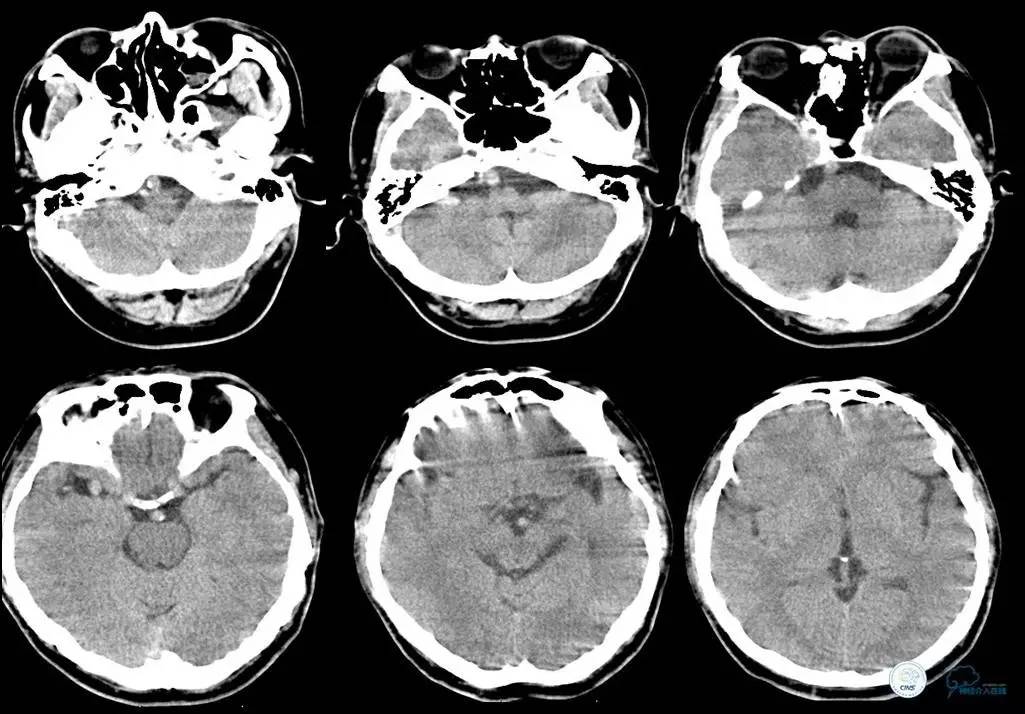

▼头CT

▼心电图:窦性心律,T波异常,心肌缺血改变。

血常规:白细胞为16.45×109/L,中性粒细胞为84.99%。

离子:钾为3.21mmol/L,镁为1.13mmol/L。

血糖:12.3mmol/L。

心肌酶:乳酸脱氢酶为187IU/L,肌钙蛋白、肌红蛋白、CK、CK-MB均正常。

凝血四项:凝血酶原时间为15.3s,活化部分凝血酶原时间为43.0s。

2014年12月15日22时50分

患者言语不清、右侧肢体麻木无力等症状缓解,但四肢末端厥冷。心电监护示,SPO2为99%,P为65次/分,R为18次/分,BP为103/60mmHg。T为35.5℃。

初步诊断为短暂性脑缺血发作。追问患者家属病史,入院前曾有大汗,未进食,低血容量性休克不除外。补液纠正休克。

2014年12月16日00时20分

患者精神差,全身不适,右肩背部疼痛,呕吐3次,呕吐物为胃内容物,排便2次,无黑便,四肢末端冰冷较前缓解。心电监护示,SPO2为93%,P为62次/分,R为18次/分,BP为101/55mmHg。T为36.2℃。急查心肌酶示CK、CK-MB正常。

2014年12月16日05时

患者上腹部背部疼痛剧烈,予氯诺西康肌注。便血2次,鲜红色,量约30ml。心电监护示,SPO2为98%,P为67次/分,R为18次/分,BP为125/66mmHg。肝功能示,总蛋白为53g/L。肾功能示,尿素氮为10.6mmol/L,肌酐为170umol/L。血淀粉酶为113U/L。血常规示,血红蛋白为145.8g/L,中性粒细胞为14.33×109/L,白细胞为15.43×109/L,红细胞为4.42×1012/L。腹部超声示,胆囊结石。